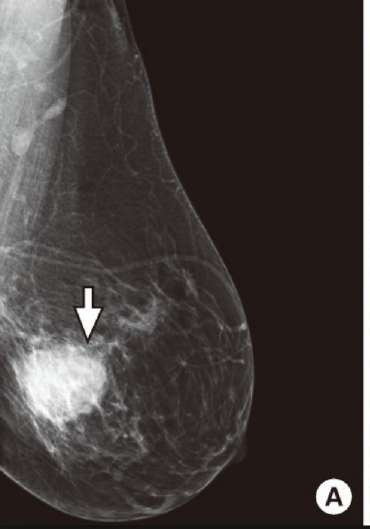

breast cancer mammogram is in which plane?

1- medial lateral oblique MLO ( pectoralis muscle and axillary vessels)

2- cranio-caudal

medial lateral oblique MLO

CC

craniocaudal

The typical high-risk finding will be a speculated mass with abnormal architecture & asymmetry, with clustered micro- calcification

breast cancer means:

irregular margin

speculated mass